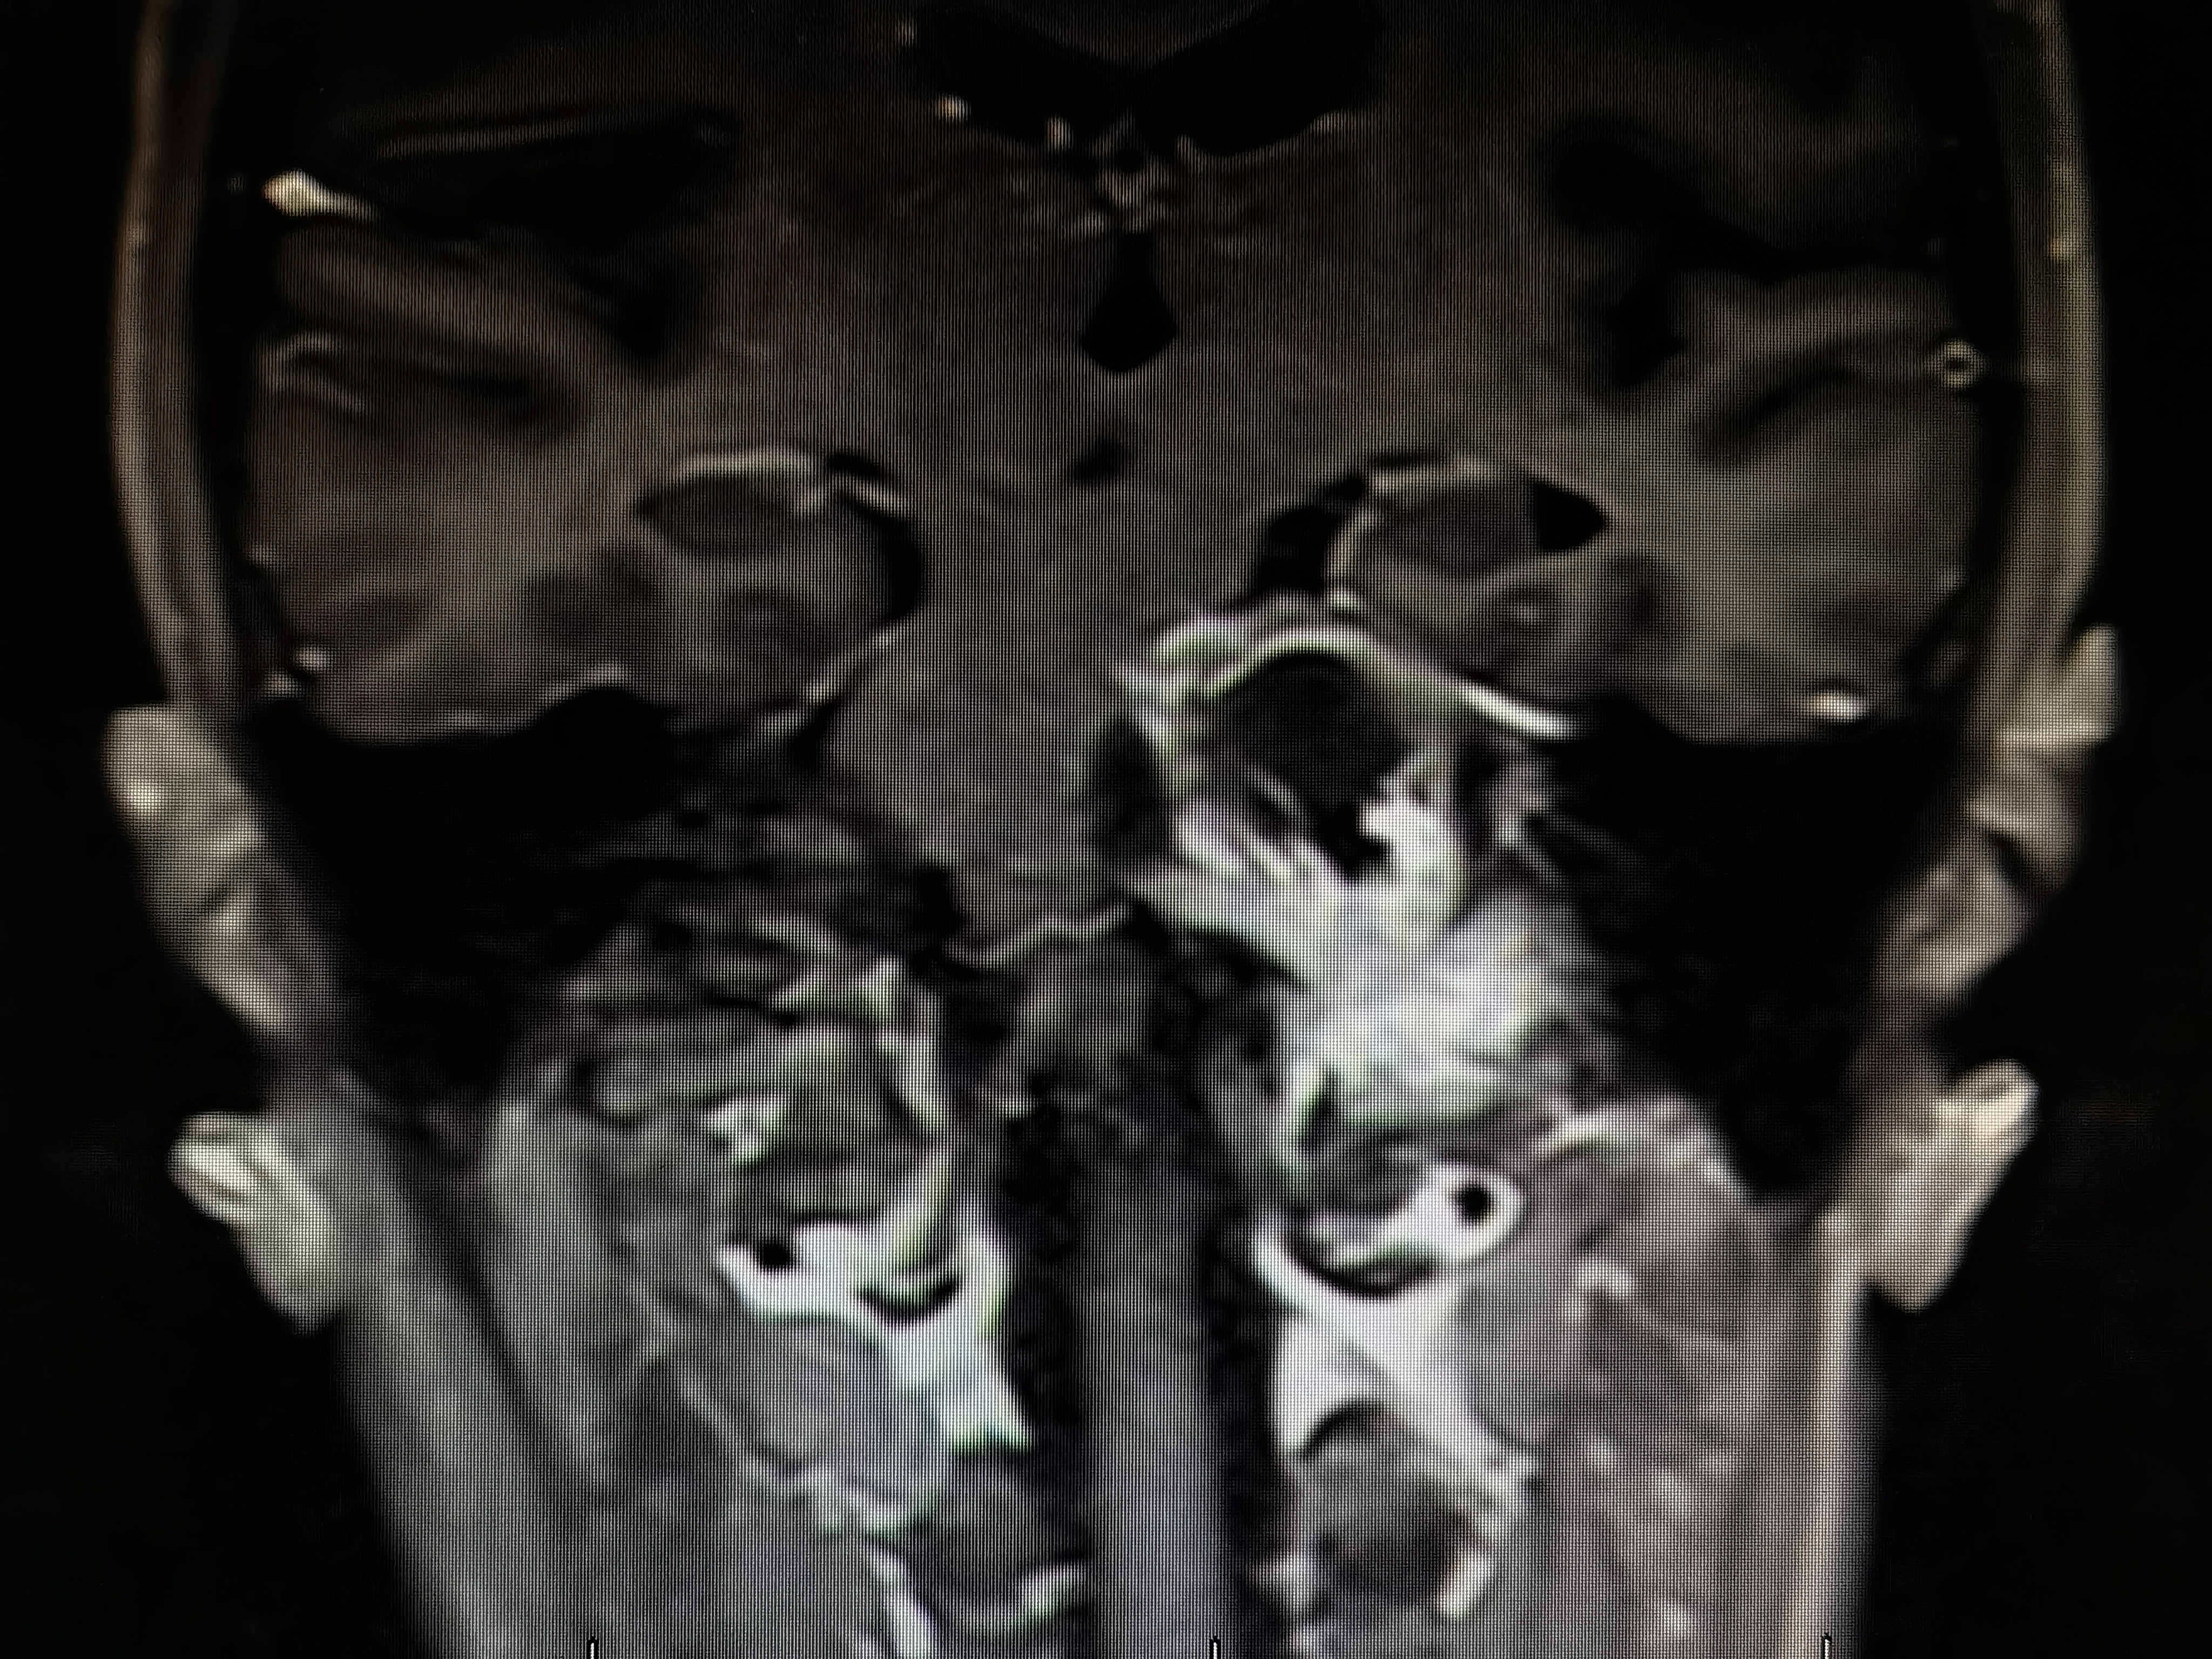

术前磁共振